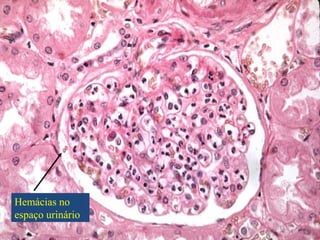

Hemácias no

espaço urinário

Síndrome Nefrítico